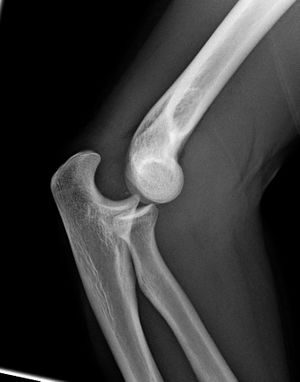

المرفق إنگليزية: Elbow هي عظمة مفصلية تربط عظمة العضد مع عظمتي الزند و الكعبرة. وتكون أماكن الالتقاء الثلاثة، ثلاثة مفاصل أصغر وتسمح هذه المفاصل الصغيرة بحركات معينة، حيث يسمح مفصلا العضد ـ الزند والعضد ـ الكعبرة للشخص بثني الساعد إلى أعلى وأسفل، بينما يسمح مفصلا الكعبرة ـ الزند والعضد ـ الكعبرة بدوران الساعد وكذلك راحة اليد أعلى وأسفل.

يحيط بمفصل الكوع كبسولة من نسيج متين. وتقوم هذه الكبسولة مع عدد من الأنسجة القوية الحبلية الشكل التي تُعرف بالأربطة بالمحافظة على العظام في أماكنها. ويعمل السائل الزيلي بمثابة مزلق لتقليل الاحتكاك عند الكوع.

| Joint | From | To | Description |

| humeroulnar joint | trochlear notch of the ulna | trochlea of humerus | Is a simple hinge-joint, and allows of movements of flexion and extension only. |

| humeroradial joint | head of the radius | capitulum of the humerus | Is a hinge-joint joint. |

| proximal radioulnar joint | head of the radius | radial notch of the ulna | In any position of flexion or extension, the radius, carrying the hand with it, can be rotated in it. This movement includes pronation and supination. |